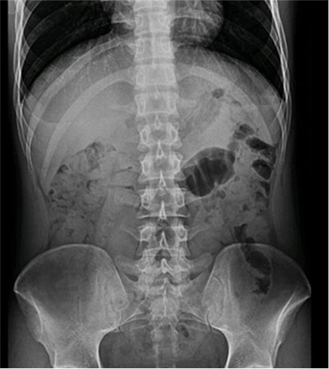

臨床圖片

微信圖片_20210927001105